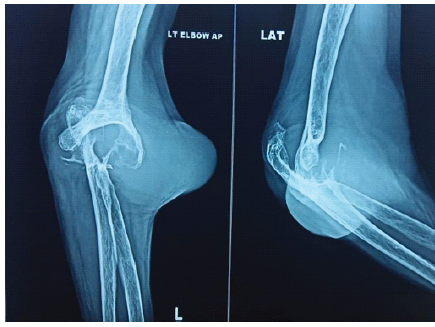

Neurovascular examination was unremarkable. Plain radiographs demonstrated advanced joint destruction (Martini-Stage 4) (Fig. 2) [4].

Figure 2: Plain radiographs demonstrated advanced joint destruction (Martini-Stage 4).